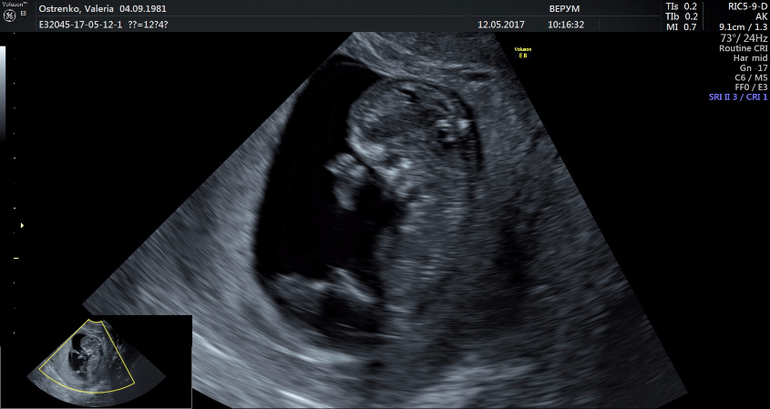

Кто разбирается гляньте под кат, УЗИ в 12 нед. может кто-что скажет

Я конечно понимаю что 50/50 но просто уж очень интерестно)))